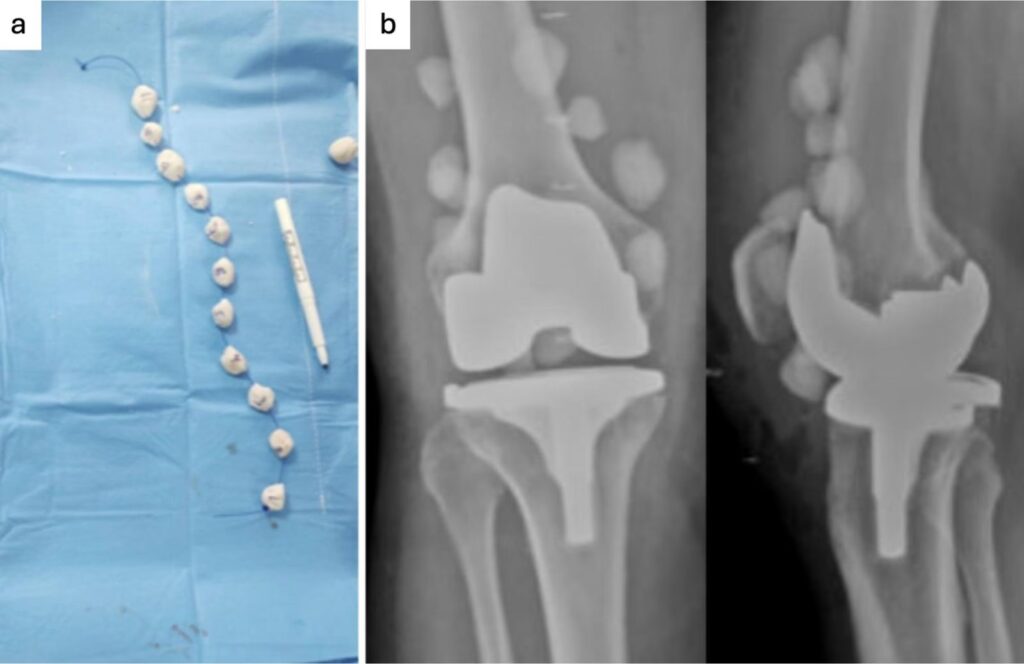

En muchos casos, los antibióticos por sí solos no son suficientes. La cirugía es necesaria para extirpar todo el tejido óseo muerto o infectado, así como cualquier material extraño (como placas, tornillos o prótesis) que pueda estar sirviendo de refugio para las bacterias. Este procedimiento se conoce como desbridamiento. El espacio vacío que queda puede rellenarse con injertos de hueso o materiales especiales que liberan antibióticos localmente para ayudar a la curación.

Esta es una de las complicaciones más serias de la cirugía de reemplazo articular. El tratamiento suele implicar una o dos cirugías: una para retirar la prótesis infectada y limpiar a fondo la zona, seguida de un largo ciclo de antibióticos. Una vez que la infección está controlada, se puede realizar una segunda cirugía para implantar una nueva prótesis.